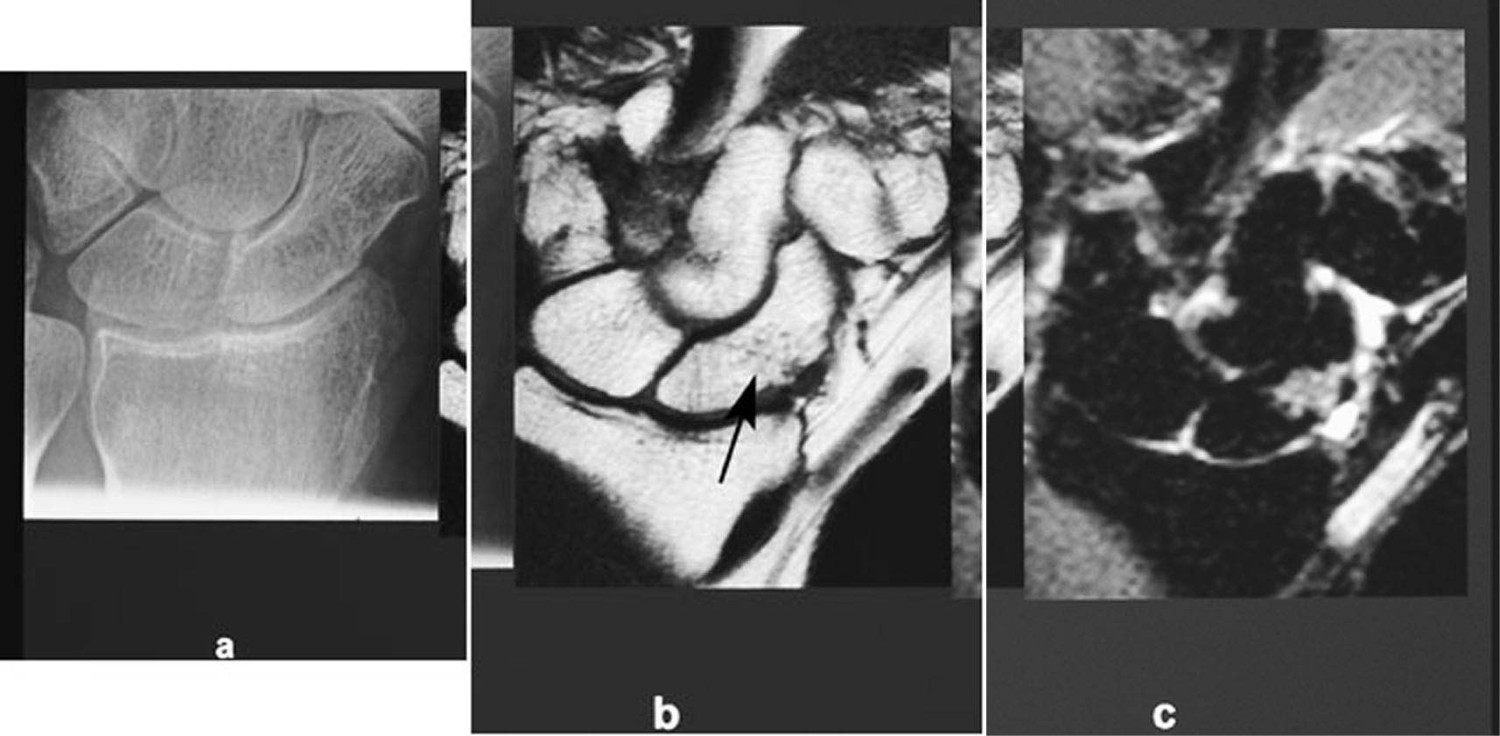

MR håndledd/håndrotsknokler

Ved konvensjonell røntgen kan det være vanskelig å diagnostisere fraktur i os scaphoid. Tidligere ble pasienter gipset og kontrollert etter 14 dager. Dette ble gjort for å forhindre en utvikling av proksimal nekrose. Ved mistenkt fraktur og negativ røntgen utfører vi nå MR-undersøkelse som øyeblikkelig hjelp, hvor vi ser på alle håndrotsknokler, distale radius og ulna og ikke minst de periartikulære ligamentene (fig 16). Rupturer av disse vil ofte forklare pasientens smerter når det ikke foreligger fraktur (12).

MR er også nyttig ved spørsmål om skade av triangulærbrusk og avaskulære nekroser av håndrotsknokler i tidlig fase.